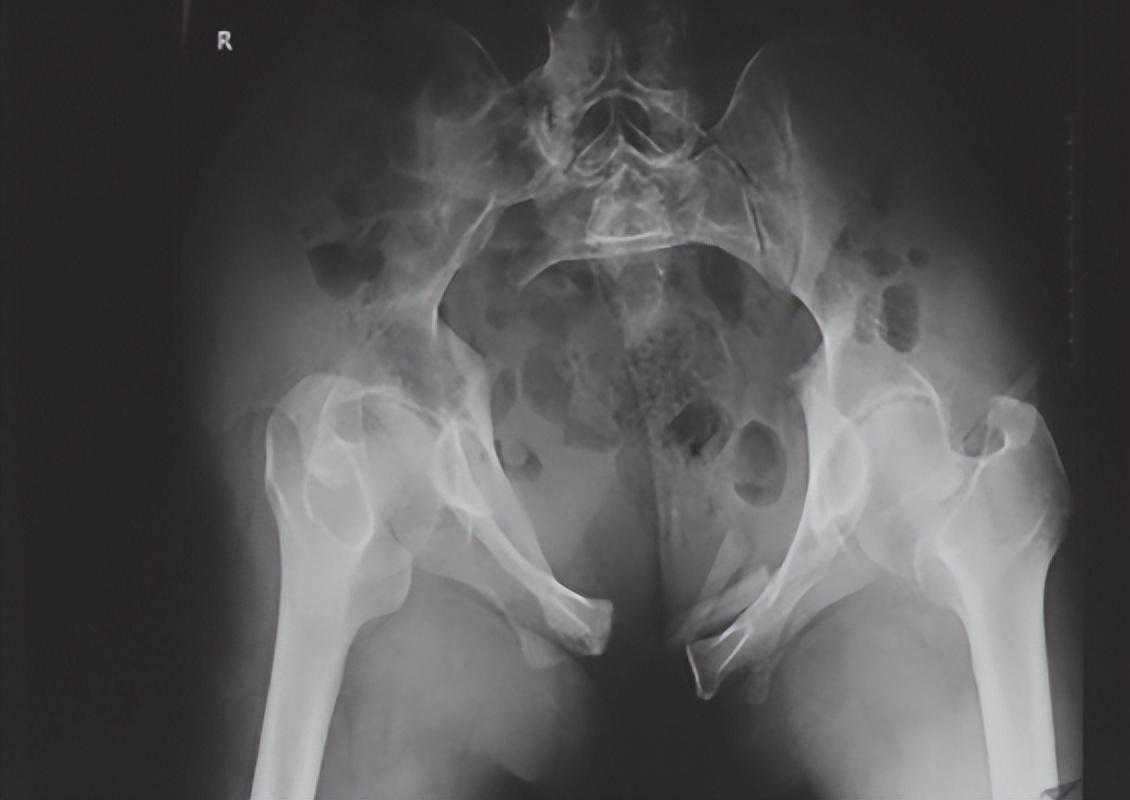

1、骨盆前后位X线检查(骨盆正位X线检查):

最为常用,患者仰卧,射线呈前后方向垂直投射,骨盆入口边缘与躯干纵轴呈45°~60°夹角。该位像基本能了解骨盆前后环骨折及骶髂关节骨折脱位情况。可用于鉴别骶骨、骨盆髋臼、近端股骨等部位骨折(图1)。

图1骨盆前后位X线片可见左侧骶髂关节骶骨及髂骨面局部骨质断裂,关节间隙增宽,左侧耻上、下支骨折,累及耻骨联合左侧缘。